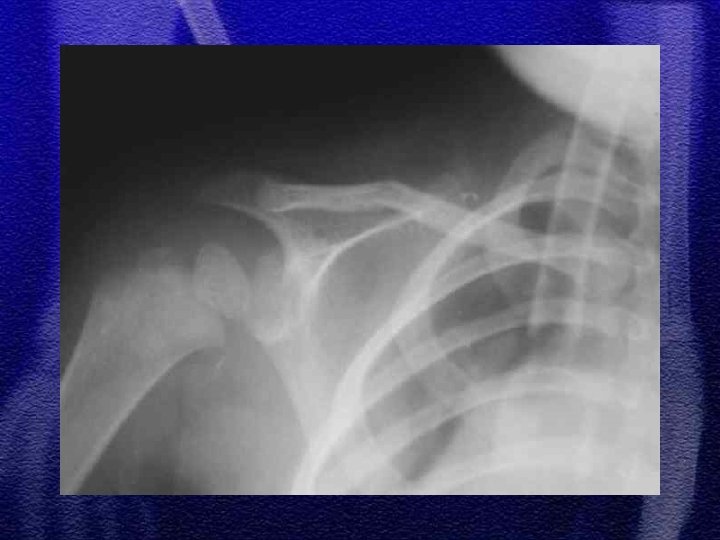

§ Najczęściej dotyczą trzonu § Złuszczenia nasad typ I lub II wg Saltera-Harrisa § Klasyczne urazowe zwichnięcia w stawie barkowoobojczykowym z uszkodzeniem więzadeł kruczo – barkowych występuje jedynie u dzieci starszych, bardzo rzadko

1. złamanie szyjki chirurgicznej (przynasady) 2. zwichnięcie barku występuje u dzieci wyjątkowo rzadko, w starszej grupie wiekowej 3. u dzieci młodszych złuszczenie typ I, u dzieci starszych typ II 4. leczenie: jednoczasowa repozycja zamknięta, wyciąg szkieletowy, leczenie operacyjne rzadko 5. istnieje bardzo duża możliwość przebudowy kości w tej okolicy